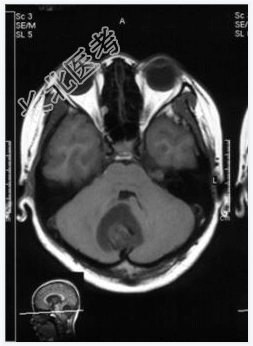

- [材料题] 患者,女性,19岁,因眩晕伴呕吐1周入院。体检:眼震,步态不稳,余未见异常。做头颅MRI检查。

- 简答题1、诊断及依据是什么?

- 简答题2、鉴别诊断有哪些?